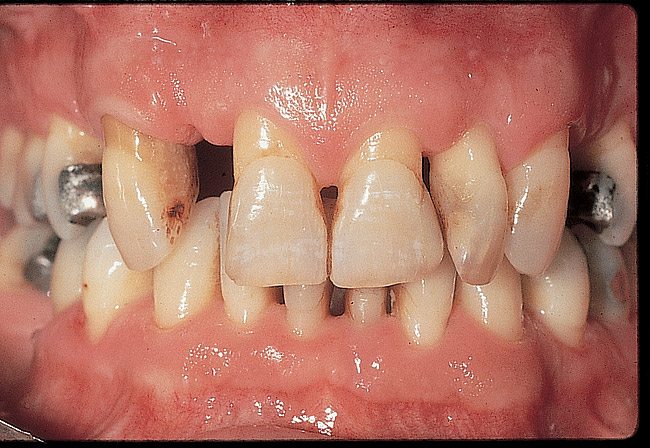

Figure 12  Preoperative facial view demonstrating maximum tooth display.

Figure 12

Figure 13  Preoperative intraoral facial view.

Figure 13